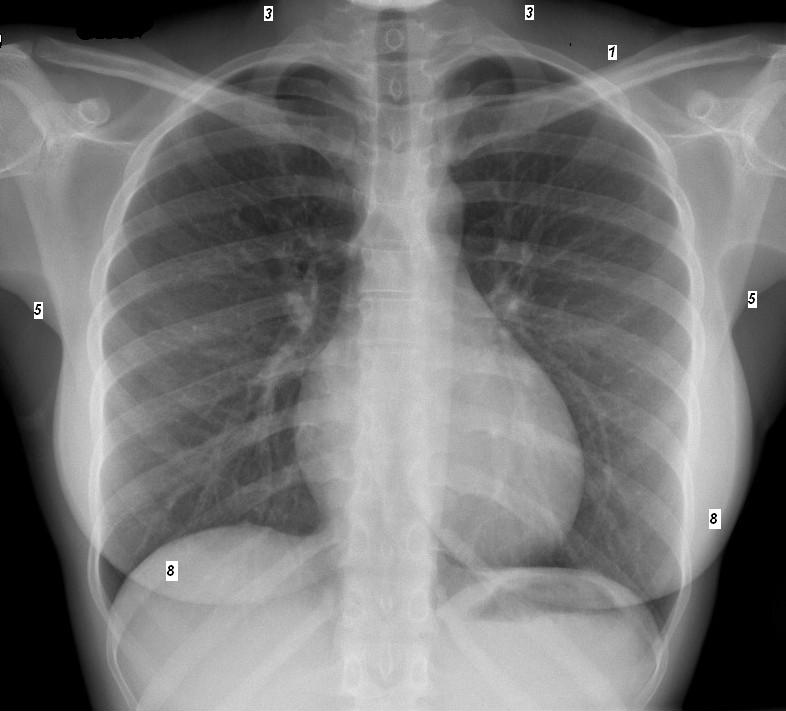

| Les images ce qui peut en pieges du cliche

de face : -1 Ombre accompagnement de la 2e

cote

-2 Ombre accompagnement de la clavicule

-3 Ombre de muscle sterno cleido-mastoidien

-4 Scissure azygos

-5 Parties molles du creux axillaire .

-6 Ombre de artere sous claviere

-7 Mamelon des hommes

- 8 Ombre des deux seins.

-9 Ombre des omoplates

-10 Calcification chondrosternales |